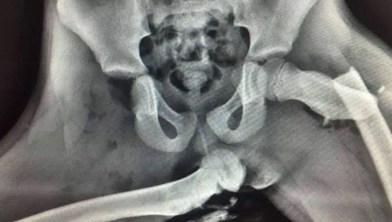

Icon T News Horrifying x-ray shows 'life-changing' effects of resting feet on car dashboard Horrifying x-ray shows 'life-changing' effects of resting feet on car dashboard